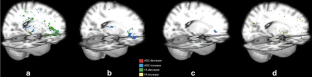

Fig. 3